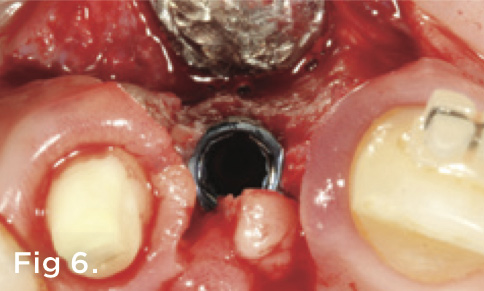

Fig 6. A papilla-sparing surgical incision design was used to preserve the interdental tissues during implant placement.

Figure 6